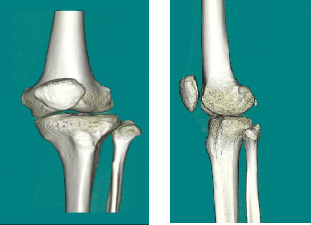

MRI 装置の撮影画像

頭の画像

膝や腰椎の画像